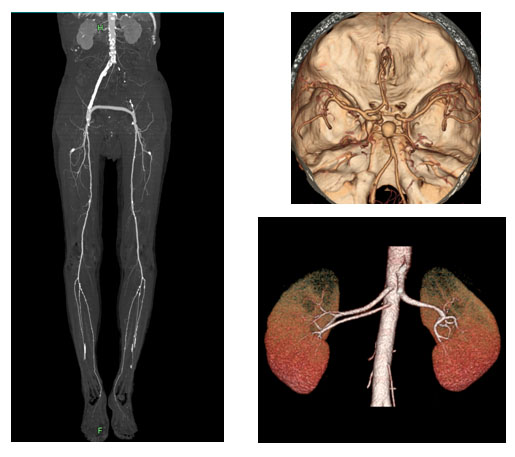

복부 CT(Computed Tomography)는 방사선과 컴퓨터 기술을 결합하여 신체 내부 구조를 3차원으로 시각화하는 영상 진단 방법입니다. 일반적인 X-ray와는 차별화된 측면에서, 복부 CT는 단면 이미지를 연속적으로 수집하여 더욱 정밀한 진단이 가능합니다. 그러므로 의사들은 이를 활용해 매우 다양한 복부 질환을 진단하며, 이를 통해 조기 발견 및 치료 방안을 신속하게 결정할 수 있습니다.

복부 CT 장비는 링 형태의 기계 내부에 방사선 투사 장치와 감지기가 내장되어 있습니다. 환자는 이 링 내부에 누워 있으며, 장비가 부드럽게 회전하면서 단면 이미지를 촬영합니다. 각각의 이미지들은 컴퓨터 소프트웨어에서 합쳐져 3차원의 고해상도 이미지를 생성하게 됩니다. 이러한 과정을 통해 의사는 대장, 간, 췌장, 신장 등 복부 각 장기의 상태를 면밀히 살펴볼 수 있습니다.

신장은 인체의 대사 노폐물을 제거하고 수분 및 전해질 균형을 유지하는 중요한 역할을 합니다. 신장에 문제가 발생하면 체내의 여러 기능이 부정적인 영향을 받을 수 있습니다. 복부 CT는 신장 결석, 신장 종양 및 기타 신장 관련 질환을 진단하는 데 도움을 줍니다.

신장 결석은 신장에서 형성된 경결된 물질로, 통증을 유발할 수 있습니다. 복부 CT는 결석의 위치와 크기를 정확하게 파악할 수 있으며, 이 정보를 바탕으로 적절한 치료 방법을 결정하는 데 매우 중요합니다. 결석이 발견되면, 물리치료, 약물 치료, 혹은 필요 시 수술이 고려될 수 있습니다. 신장 결석은 수분 보충과 균형 잡힌 식사를 통해 예방할 수 있으므로, 생활 방식의 변화 또한 동반되어야 합니다.